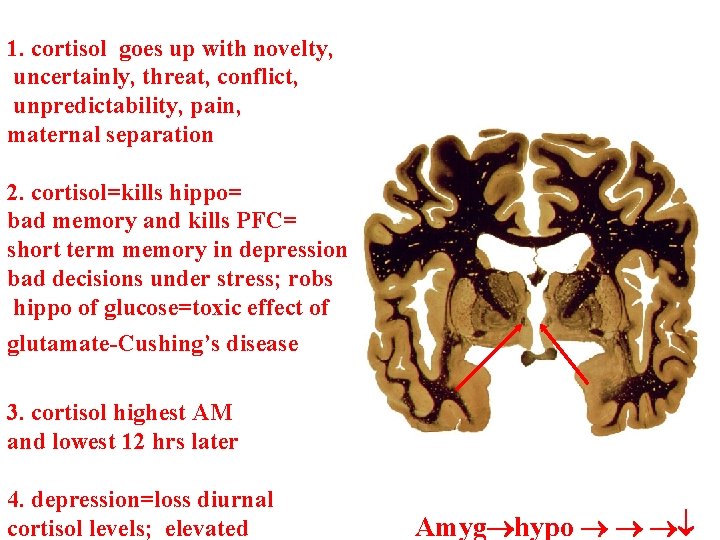

1. cortisol goes up with novelty, uncertainly, threat, conflict, unpredictability, pain, maternal separation 2. cortisol=kills hippo= bad memory and kills PFC= short term memory in depression bad decisions under stress; robs hippo of glucose=toxic effect of glutamate-Cushing’s disease 3. cortisol highest AM and lowest 12 hrs later 4. depression=loss diurnal cortisol levels; elevated Amyg hypo